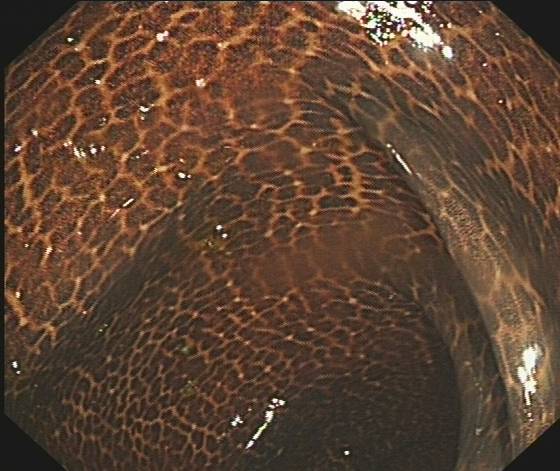

结肠镜检查时 , 医生发现王奶奶的肠子布满了棕黑色的花纹 , 像“蛇皮”一样 , 十分骇人 。 王奶奶说 , 因为自己便秘一直不见好 , 听人说通便酵素很有用 , 就买来试试 。 王奶奶发现用了酵素以后 , 上厕所果然通畅了很多 。 就这样 , 王奶奶开始依赖酵素 , 一直吃了三年 。

王奶奶的结肠黏膜

“这是典型的结肠黑变病” , 余杭三院消化内科(内镜中心)副主任杜叶春说 。 正常的结肠黏膜就像口腔黏膜一样是淡红色的 , 看起来光滑平坦 , 黏膜表面的小血管纹理清晰可见 。 而结肠黑变病的肠黏膜色泽为棕色、褐色甚至黑色 , 有豹纹、蛇皮一样的条状纹 , 消化内科医生常称为“黑肠子” 。